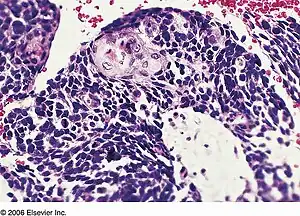

Combined small-cell lung carcinoma

| Combined small cell lung carcinoma containing a component of squamous cell carcinoma | |

Combined small cell lung carcinoma (or c-SCLC, and rarely rendered as "small-cell lung carcinoma") is a form of multiphasic lung cancer that is diagnosed by a pathologist when a malignant tumor arising from transformed cells originating in lung tissue contains a component of small cell lung carcinoma (SCLC) admixed with one (or more) components of non-small cell lung carcinoma (NSCLC).[1][2][3]